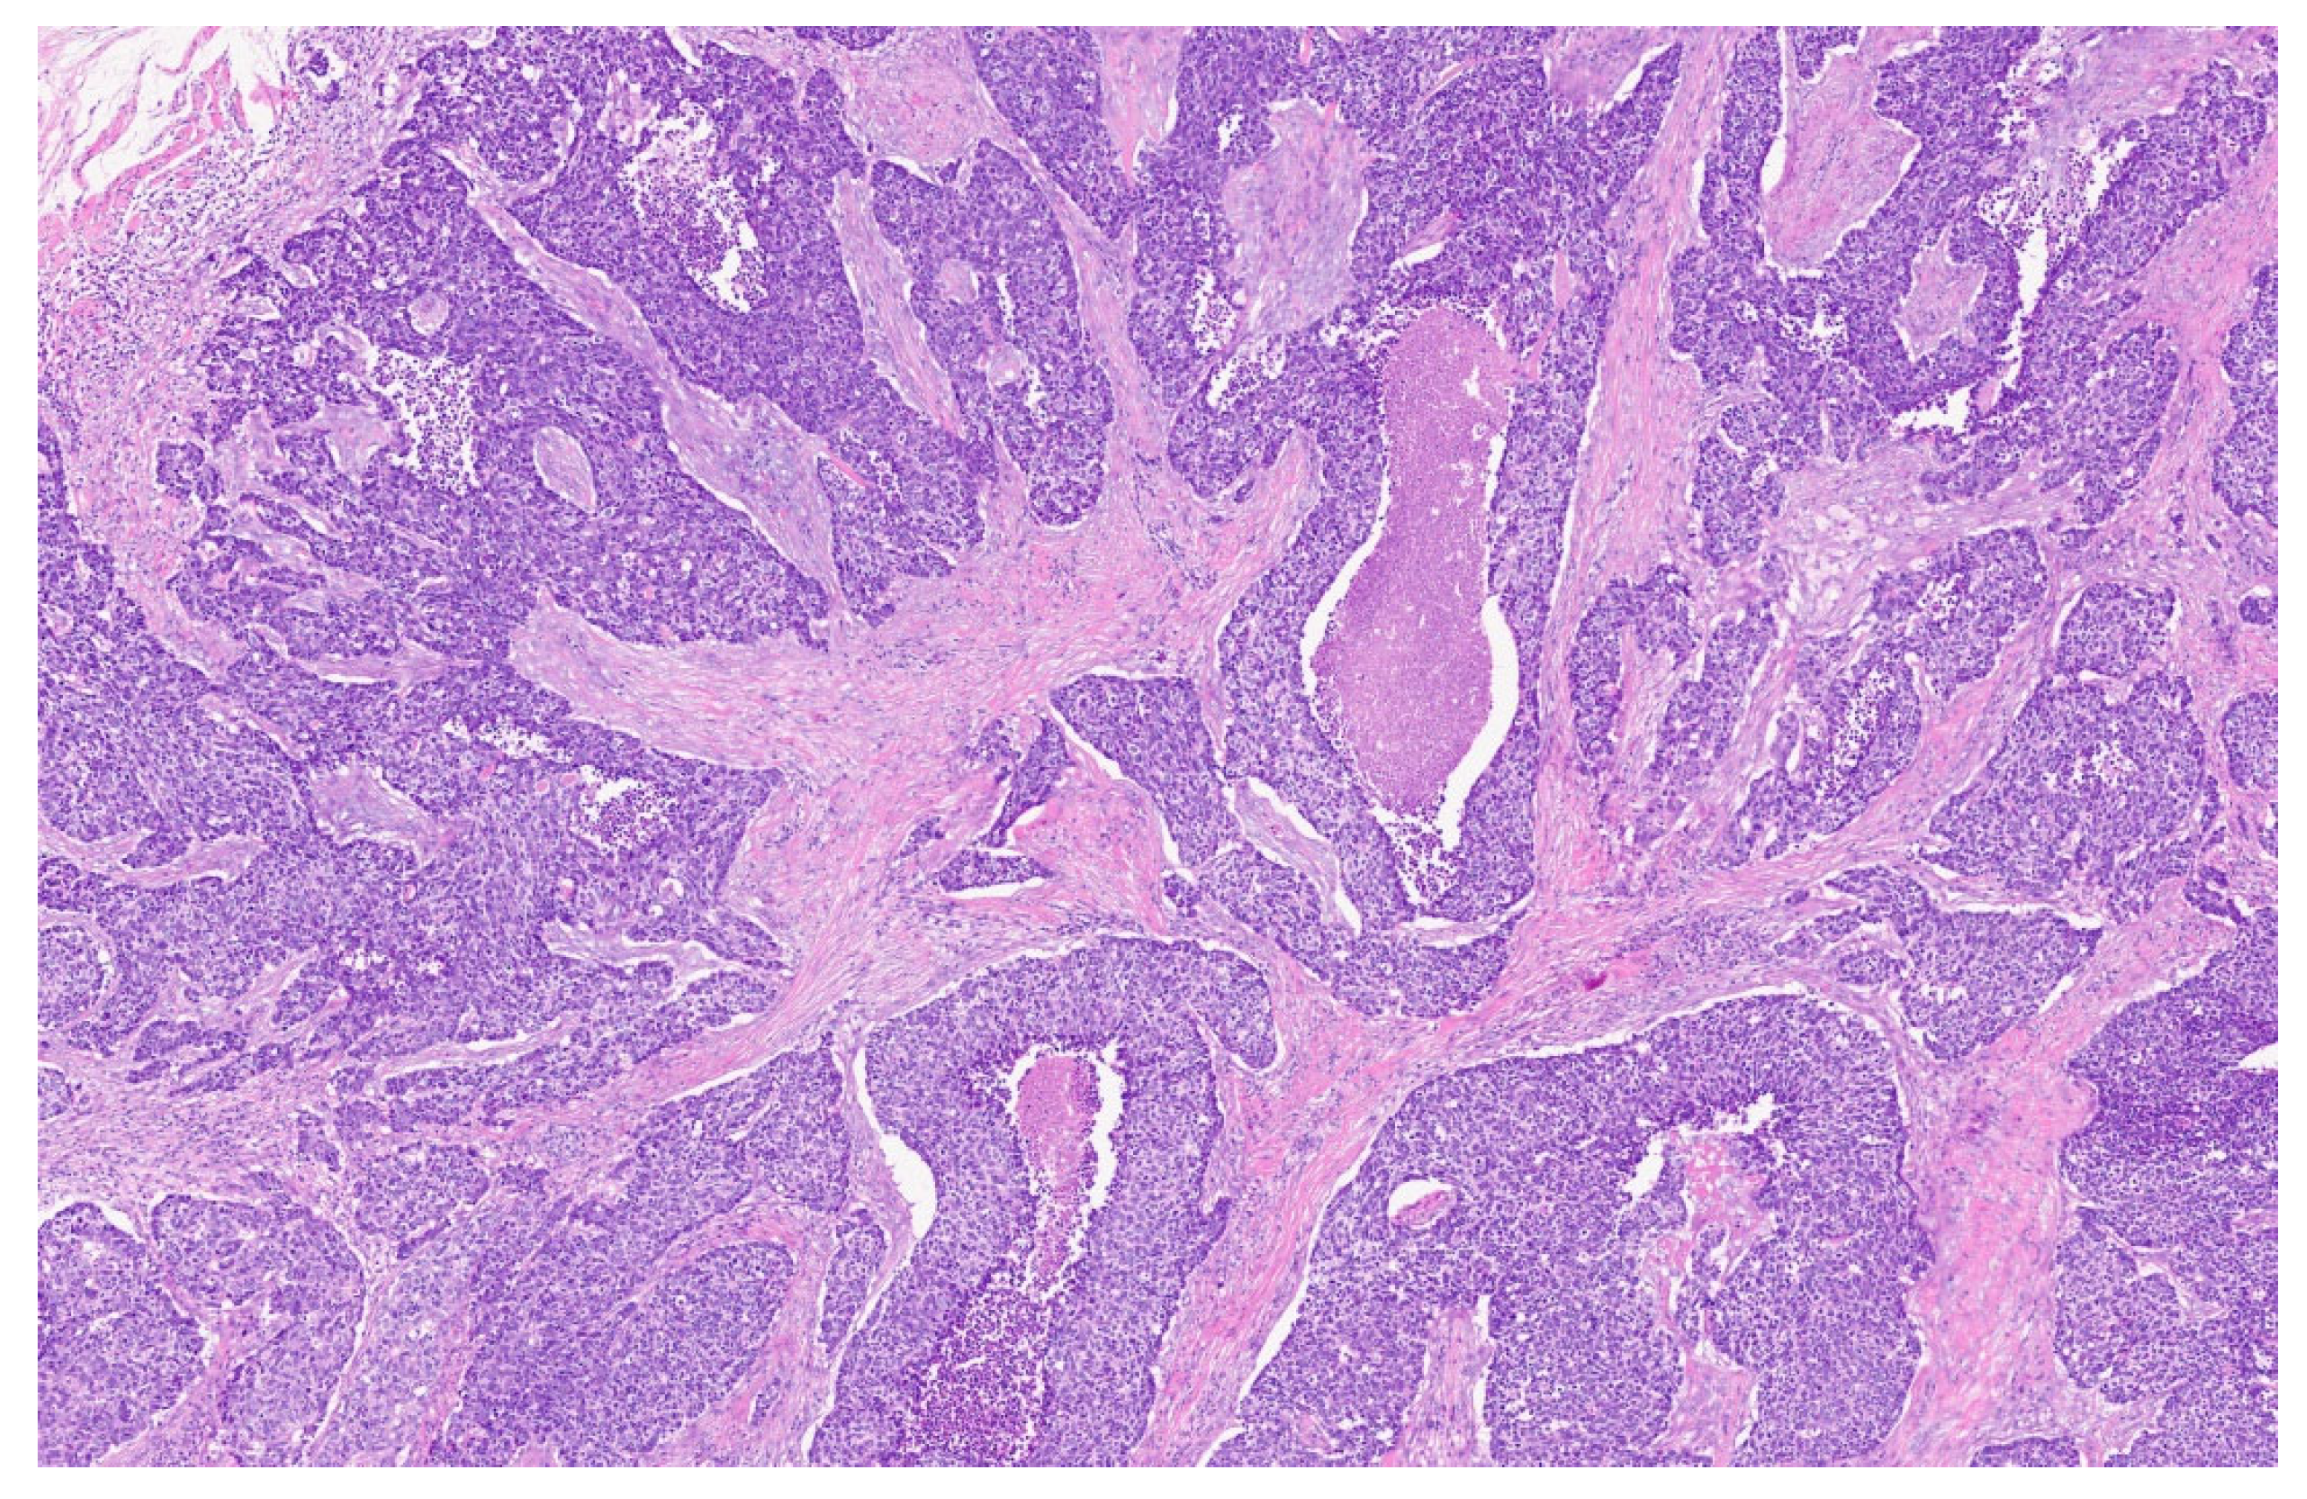

2. Case Presentation